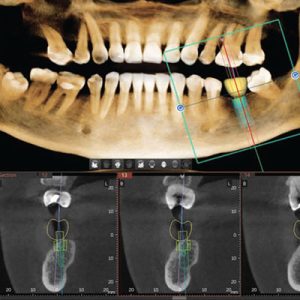

3D CBCT

snimanje nove generacije

3D snimanje zuba omogućava detaljan uvid za širok spektar stomatoloških procedura.

3D endo

samo jedan zub

Uz 3D ENDO dobijate precizno 3D snimanje zuba za usko definisane željenje regije.

4 različte veličine

polja snimanja

Inovativni lučni FOV (Field of View) pruža širi i potpuniji prikaz dentalnih struktura.